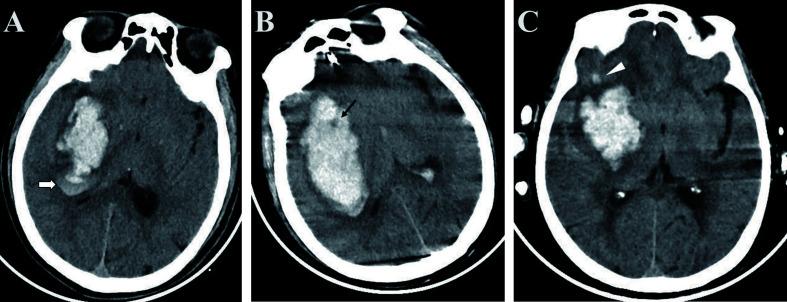

This meta-analysis aimed to assess the efficacy of radiomics using non-enhanced computed tomography (NCCT) for predicting hematoma expansion in patients with spontaneous intracerebral hemorrhage.

Ten articles comprising a total of 1525 patients were quantitatively analyzed for hematoma expansion after cerebral hemorrhage using radiomics. Based on the included studies, the mean RQS was 14.4. The AUC value (95% confidence interval) of the radiomics model was 0.80 (0.76-0.83). Five articles comprising 846 patients were included in the NMA. The results synthesized according to Bayesian NMA revealed that the predictive ability of the radiomics model outperformed most of the NCCT biomarkers.

The NCCT-based radiomics approach has the potential to predict hematoma expansion. Compared to NCCT biomarkers, we recommend a radiomics approach. Standardization of the radiomics approach is required for further clinical implementation.